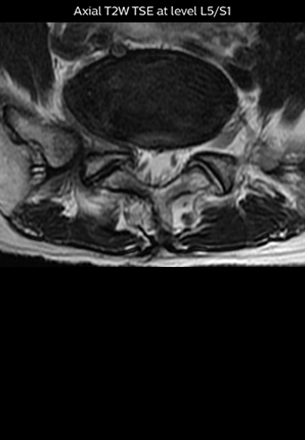

“Although symptoms of typical disc herniation and atypical hernia are very similar, the actual site of herniation is different. It is therefore important to characterize the nerve’s condition both inside and outside of the intervertebral foramina. “Conversely, if we see no abnormality in NerveVIEW, we can assume at least that there is no severe condition that requires surgery. Like this, it can help us avoid unnecessary surgery. NerveVIEW can have a tremendous impact in this way.”

“NerveVIEW is really useful for those cases where a nerve disorder is strongly suspected based on the clinical examination but our regular MRI images do not show any findings. These atypical herniations and spinal canal stenosis, occurring in 5% to 15% of the total lumbar herniation/stenosis cases are our main target when using NerveVIEW,” says Dr. Yabuki.

“The intra-luminal signal of veins, especially around the intervertebral space, can be suppressed well with NerveVIEW. As a result, we can easily observe the detailed nerve structure around the posterior ganglion,” he says. “This is why we use 3D NerveVIEW for intraforaminal stenosis and extraforaminal stenosis/herniation (lateral disc herniation). On the other hand, if herniation is suspected to exist inside the dorsal root ganglion (DRG), balanced TFE or ProSet-FFE is applied. NerveVIEW is not suitable for evaluating the median type of herniation.” The SE-EPI DWI-based method for MR neurography works well for large FOV exams like whole-body MRI, but focal examination of nerves is often limited by the attainable spatial resolution (both inplane and slice direction) and geometric distortion. “3D NerveVIEW achieves higher in-plane resolution – close to our other routine spine sequences – and the source images can be used instead of adding a fat-suppressed T2-weighted sequence,” Tanji says.